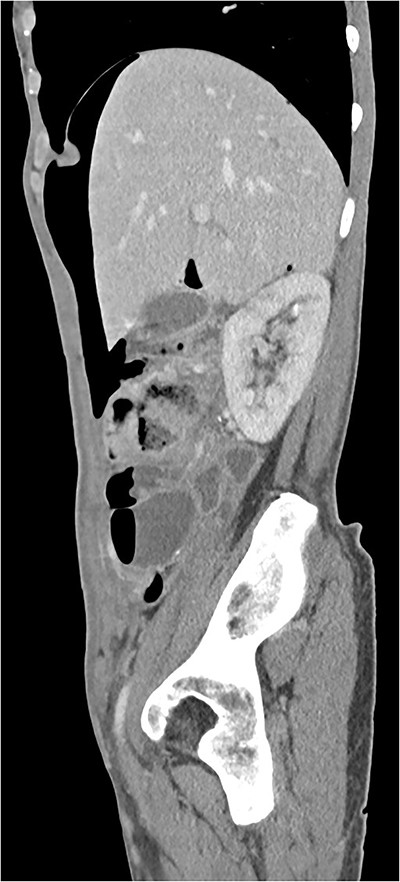

A 63-year-old woman underwent an elective hysterectomy and bilateral adnexectomy due to a large right adnexal mass (290 × 190 mm). On the sixth postoperative day, she developed nausea and vomiting, along with abdominal distension and generalized abdominal pain, without peritoneal signs or guarding. An abdominal X-ray was requested, which showed pneumoperitoneum and multiple air-fluid levels in the small intestine. Blood tests were unremarkable. An abdominal and pelvic computed tomography (CT) scan was also performed, revealing “pneumoperitoneum in a quantity above what would be expected given the postoperative timeline, with no image suggestive of hollow viscus or vaginal cuff dehiscence.” (Figs 1 and 2). Based on the clinical findings, a conservative approach was chosen. A nasogastric tube was placed, and the patient was put on a nil-by-mouth diet. Two days later, she began an oral diet and resumed intestinal transit, maintaining a favorable clinical course for the remainder of her hospital stay.